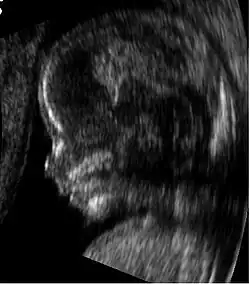

Medical ultrasound is an ultrasound-based diagnostic medical imaging technique used to visualize muscles, tendons, and many internal organs to capture their size, structure and any pathological lesions with real time tomographic images. Ultrasound has been used by radiologists and sonographers to image the human body for at least 50 years and has become a widely used diagnostic tool.[38] The technology is relatively inexpensive and portable, especially when compared with other techniques, such as magnetic resonance imaging (MRI) and computed tomography (CT). Ultrasound is also used to visualize fetuses during routine and emergency prenatal care. Such diagnostic applications used during pregnancy are referred to as obstetric sonography. As currently applied in the medical field, properly performed ultrasound poses no known risks to the patient.[39] Sonography does not use ionizing radiation, and the power levels used for imaging are too low to cause adverse heating or pressure effects in tissue.[40][41] Although the long-term effects due to ultrasound exposure at diagnostic intensity are still unknown,[42] currently most doctors feel that the benefits to patients outweigh the risks.[43] The ALARA (As Low As Reasonably Achievable) principle has been advocated for an ultrasound examination – that is, keeping the scanning time and power settings as low as possible but consistent with diagnostic imaging – and that by that principle nonmedical uses, which by definition are not necessary, are actively discouraged.[44]